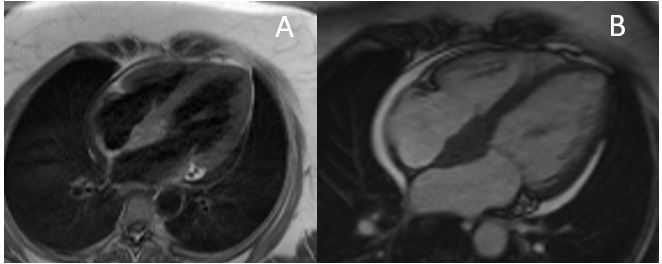

Figure 2: Short Axis T1-weighted (A) and Short Axis T2 Fat Saturation (B)